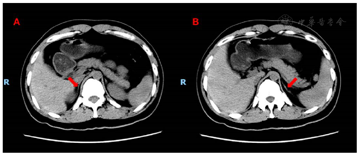

其中血尿皮质醇及ACTH结果如表1。肾上腺CT结果提示:双侧肾上腺体积缩小,几乎呈线状改变,密度未见明确异常,增强扫描均匀强化。周围脂肪间隙清晰(图1)。

患者反复发作乏力,全身多处可见色素沉着,血钠降低,血皮质醇降低且节律消失,24小时尿游离皮质醇降低,血ACTH升高,肾上腺CT提示双侧肾上腺缩小;结合上述特征,考虑患者Addsion病诊断明确。